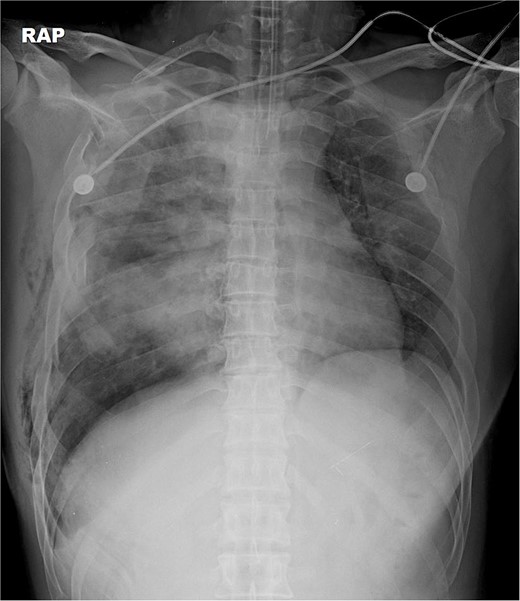

The thoracotomy incision was relatively small, ~8 cm in size, and the intercostal space was not spread to prevent further intraoperative chest wall damage. There were multiple lung lacerations in the upper, middle, and lower lobes with active bleeding. Bloody leakage continued through the avulsed parietal pleura and mediastinum. Hemostasis was achieved by suturing the deeply lacerated lung and packing with gauze (Combat Gauze ™ [Z-Medica QuikClot]) at the chest wall and mediastinum. The operation took 130 minutes. The transfusion of plasma, platelets, and red blood cells was balanced according to the following quantities: 10, 10, and 14 U, respectively. After surgery, the patient was transferred to the intensive care unit (ICU). The PaO2/FiO2 ratio was 52 mmHg with a Positive end expiratory pressure of 15 cm H2O, at a peak inspiration pressure of 30 cmH2O. ABGA showed pH 7.23, pCO2 42, and pO2 47. Veno-venous ECMO based on bilateral femoral vein cannulation was performed (Fig. 3a). Considering the patient’s hemorrhagic predisposition, heparin was not used. Disseminated intravascular coagulation (DIC) occurred along with acute renal failure. Antithrombin III infusion and continuous renal replacement therapy (CRRT) were initiated on the second hospital day. By the 5th day, oxygenation was achieved without ECMO support, followed by decannulation. On the 6th day, the second operation was performed in about 35 minutes. The gauze was removed, and no active bleeding or oozing was seen (Fig. 3b). The third operation, performed on the 13th day, was an open reduction of right ribs 3–7 for correction of flail chest and took 75 minutes (Fig. 3c). After open reduction, the flail chest improved, but the patient was not able to be weaned off the ventilator. Pneumonia and bacteremia developed. A tracheostomy was performed on the 15th day. CRRT was switched to hemodialysis, which was stopped on Day 28. The patient was discharged on the 47th day without tracheostomy. Ten months postoperatively, pulmonary function testing revealed forced expiratory volume in one second and diffusion capacity of carbon monoxide of 77% and 67% of predicted values, respectively. The chest CT and radiographs showed that the lungs had healed well, and there was no displacement of the ribs (Fig. 4). The patient recovered and returned to work.

Simple radiographs obtained after each operation. (a) Radiograph after the first operation. Gauze, which is visible as a wavy white line, was packed in the right thoracic cavity. Multifocal opacity was seen in the right lung, and there was left upper lung atelectasis. ECMO catheters were placed in the IVC. (b) Radiograph following the second operation. The right ribcage is narrowed due to displaced fractured ribs. (c) Radiograph after the third operation. Five plates were applied to the fractured ribs.